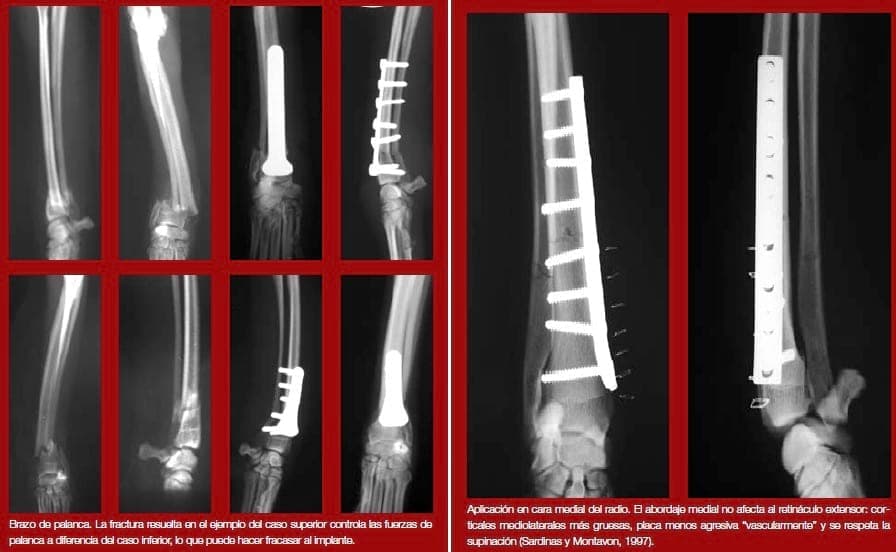

La longitud del hueso desde la fractura hasta la articulación actúa como brazo de palanca. En animales de huesos largos este efecto de brazo de palanca puede ser suficientemente importante como para fatigar la placa. En estos casos puede ser necesario añadir más de tres tornillos a cada lado del implante.

En el caso particular de las fracturas de radio, hay autores que demuestran ventajas biomecánicas con la aplicación de la placa en su cara medial frente a la tradicional aplicación craneal. Estas ventajas son: mayor resistencia del implante, corticales más anchas en sentido medio-lateral, menor molestia en las inserciones tendinosas extensoras y menor agresividad de los tornillos, a nivel vascular, por ocupar menos superficie ósea y no invadir el espacio interóseo radio-cubital.

Sardinas J.C., Montavon P.M. Use of a medial bone plate for repair of radius and ulna fractures in dogs and cats: a report of 22 cases. Vet Surg. 1997 Mar- Apr;26(2):108-13.